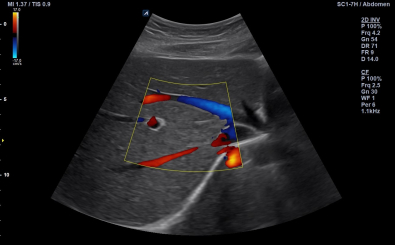

Abdomen in Color Flow mode